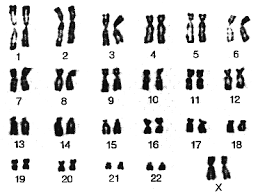

- آزمایشگاه ژنتیک

کاریوتایپ